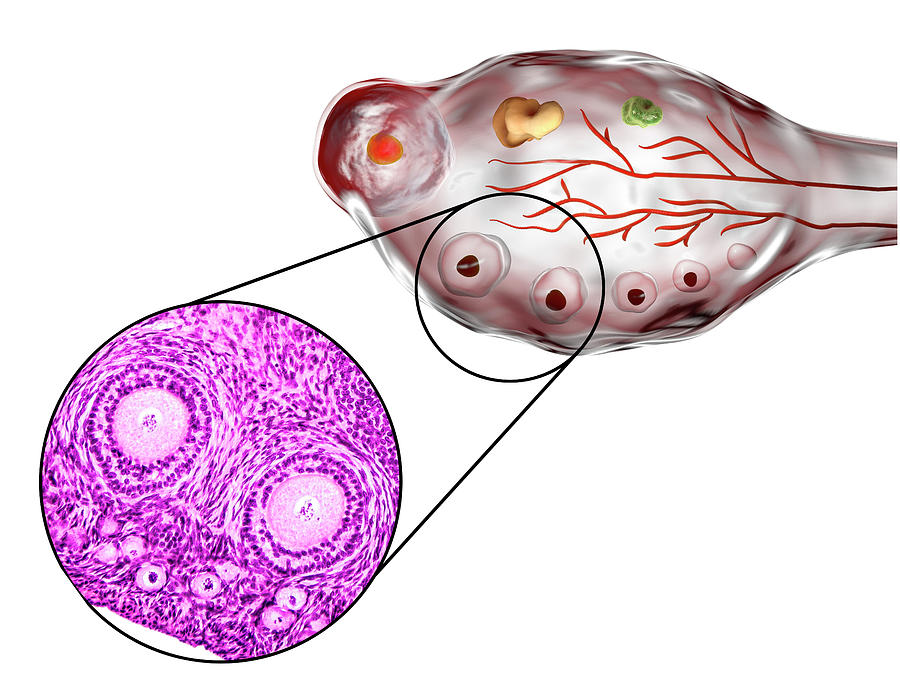

Созревание фолликула в яичнике: этапы и процессы